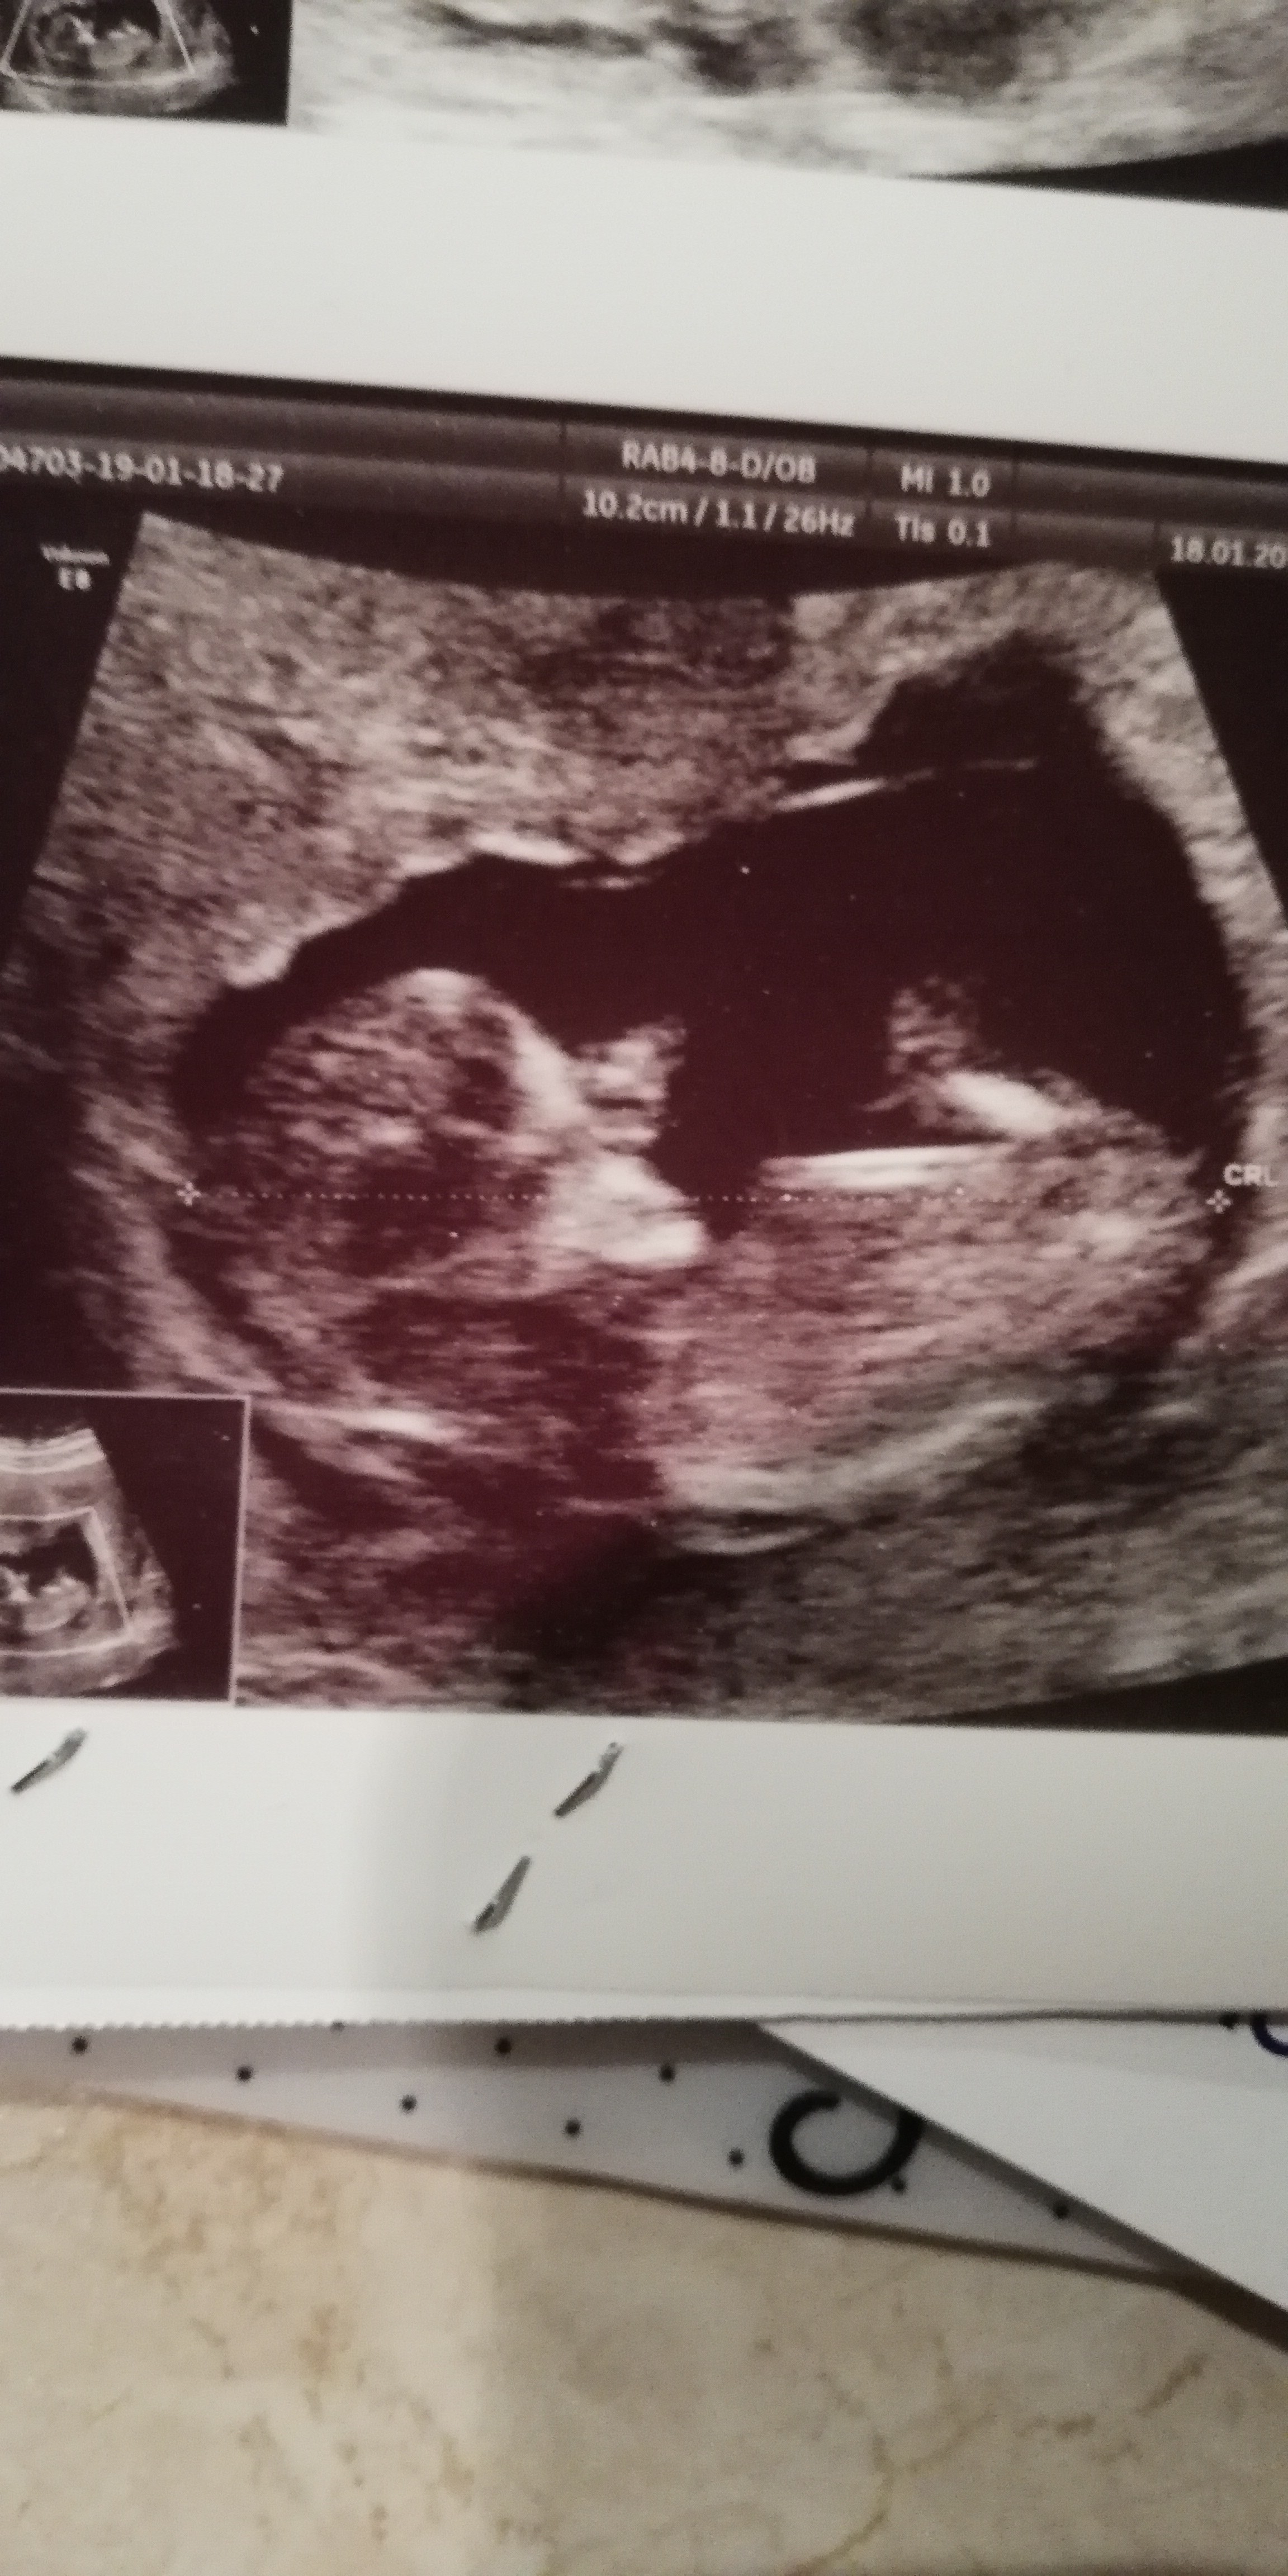

Kochana, przestań po prostu myśleć, że możesz być w ciąży! Wklejam Ci usg w 12 tygodniu, normalnie widać dziecko! Nie ma szans, żebyś była w ciąży. Absolutnie. Wiem, że po tym co Cie spotkało to trudne, ale po prostu sama sobie powiedz, że to niemozliwe!

IMG_20190118_195704.jpg

Kochana, przestań po prostu myśleć, że możesz być w ciąży! Wklejam Ci usg w 12 tygodniu, normalnie widać dziecko! Nie ma szans, żebyś była w ciąży. Absolutnie. Wiem, że po tym co Cie spotkało to trudne, ale po prostu sama sobie powiedz, że to niemozliwe! Zobacz załącznik 1036182

Na zdjęciu przesłanym przez Panią widać dość dokładnie człowieka. okres mi się dalej spóźnia i dalej bolą mnie piersi. Pisząc do Pani doktor kazała znowu zrobić betę HCG, a ostatni raz robiłam 2 tygodnie temu wiec nie wiem po co jak ta sama pani doktor 1,5 tygodnia temu wykluczyła ciąże. W macicy na pewno mam pusto i w okolicach narządów płciowych też, jak mogłaby być sugerowana ciąża pozamaciczna. Także trochę stresują dlaczego musiałam dzisiaj powtórzyć badanie jak od 19 lipca nie miałam styczności z sytuacją, która mogła by spowodować ciąże. To było tylko ten jeden jedyny raz. Jedynie co pomyslałam to w sumie jak nic nie robiłam to wynik będzie podobny do tego co w zeszłym tygodniu. Podobny bo zrobiłam w innym miejscu niż zwykle, ale bardzo się stresuje całą tą sytuacją. Może to usg do odbytowe nie jest tak dokładne, może dziecko jest gdzieś poza macicą. Tego się najbardziej boje że lekarze nie moze nie umieją zlokalizować. Ale przez 2 miesiące miałam normalnie, okres raz wywołany był luteiną 50, a raz sam przyszedł. Najbardziej martwi mnie to że od wtorku mam trądzik na twarzy, a od środy koła mnie piersi coś jak zespół przedmiesiączkowy, tylko dość długo trwa i to jest najgorsze. Chciałbym, że od tego jednego niedobrego zdążenia minęły już 9 miesięcy, wtedy mogę być spokojna. Boje się też babrania usg jamy brzusznej, że tam niespodziewanie lekarz coś zauważy. Badanie mam z tzw. przez lekarzy problemów pokarmowych oraz lekką kreskę negre też z tego. Obawy mam też przez historie takie jak np. kobieta była w ciąży a dowiedziała się tuż przed porodem bo testy domowe ani Beata HCG nie wychodziły dodatnie. Takich przypadków jest mało, ale jednak są i boje się, że to właśnie ja jestem wy dziwnym przypadkiem. Chociaż z tego co wyczytałam w internecie, to w takim tygodniu beta już nie rośnie tylko się zatrzymuje. Też znalazłam historie kobiet, które przez pierwsze miesiące ciąży miały okres. U mnie okres w sierpniu był dość obfity, we wrześniu średnio zatrzymywał się, ale był. Pomyślałam w sumie, że w lipcu też taki był to moze coś z jamnikiem, ale to by ważyło na to że teraz powinnam mieć normalnie. Nie umiem normalnie żyć, a bardzo bym chciał być spokojna i zająć się tym co powinnam, a nie martwienia się, co powiem ludziomrodzinie, znajomym jak okaże się że to są pomyłki i będę musiała ze wszystkiego zrezygnować z powodu wstydu jaki jest być w ciąży bez mężczyzny i ze zmuszenia, a nie z miłości. Może Pani doktor kazała powtórzyć to badanie w celu zabezpieczenia, bo przepisałam mi Luteinę 50. Nie wiem od lipca, żyje w niepewności i strachu.